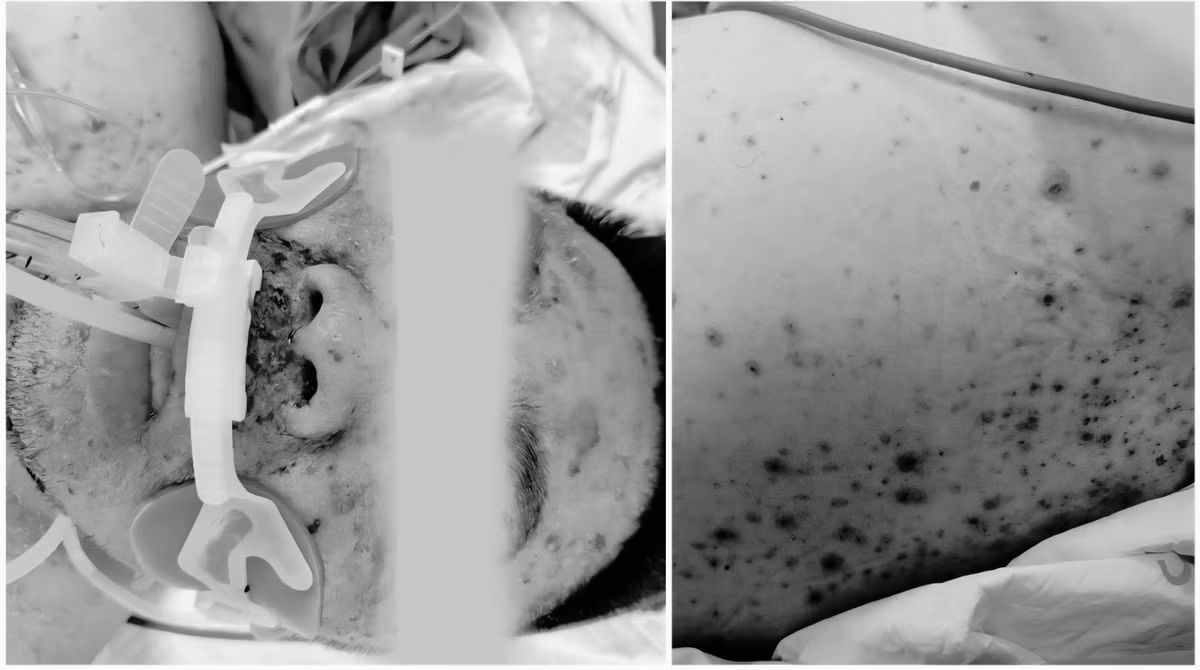

Ngày 31/7, Bệnh viện Bạch Mai cảnh báo đỏ về nỗi đau mang tên thủy đậu. Theo đó, bệnh nhân nam, 30 tuổi, vào viện trong tình trạng nguy kịch, tiên lượng xấu do biến chứng thủy đậu nặng nề.

Dù đã được điều trị tích cực bằng thuốc kháng virus và các biện pháp lọc máu hiện đại, nhưng tình trạng suy gan tối cấp, suy đa tạng, rối loạn đông máu nghiêm trọng của bệnh nhân không được cải thiện.

Bệnh nhân bị thủy đậu nguy kịch - Ảnh BVCC